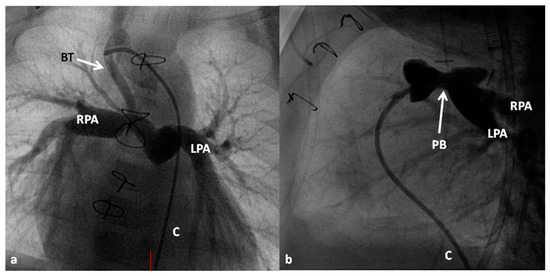

At about the age of six months, a bidirectional Glenn procedure [80] is performed. In this procedure, the superior vena cava (SVC) is disconnected from the right atrium and anastomosed to the PA so that the blood from SVC is directed into both branch PAs, thus the name bidirectional Glenn (Figure 8).

In patients with an additional persistent left SVC, a bilateral, bidirectional Glenn procedure (Figure 9) is performed especially if the bridging left innominate vein is small or absent.